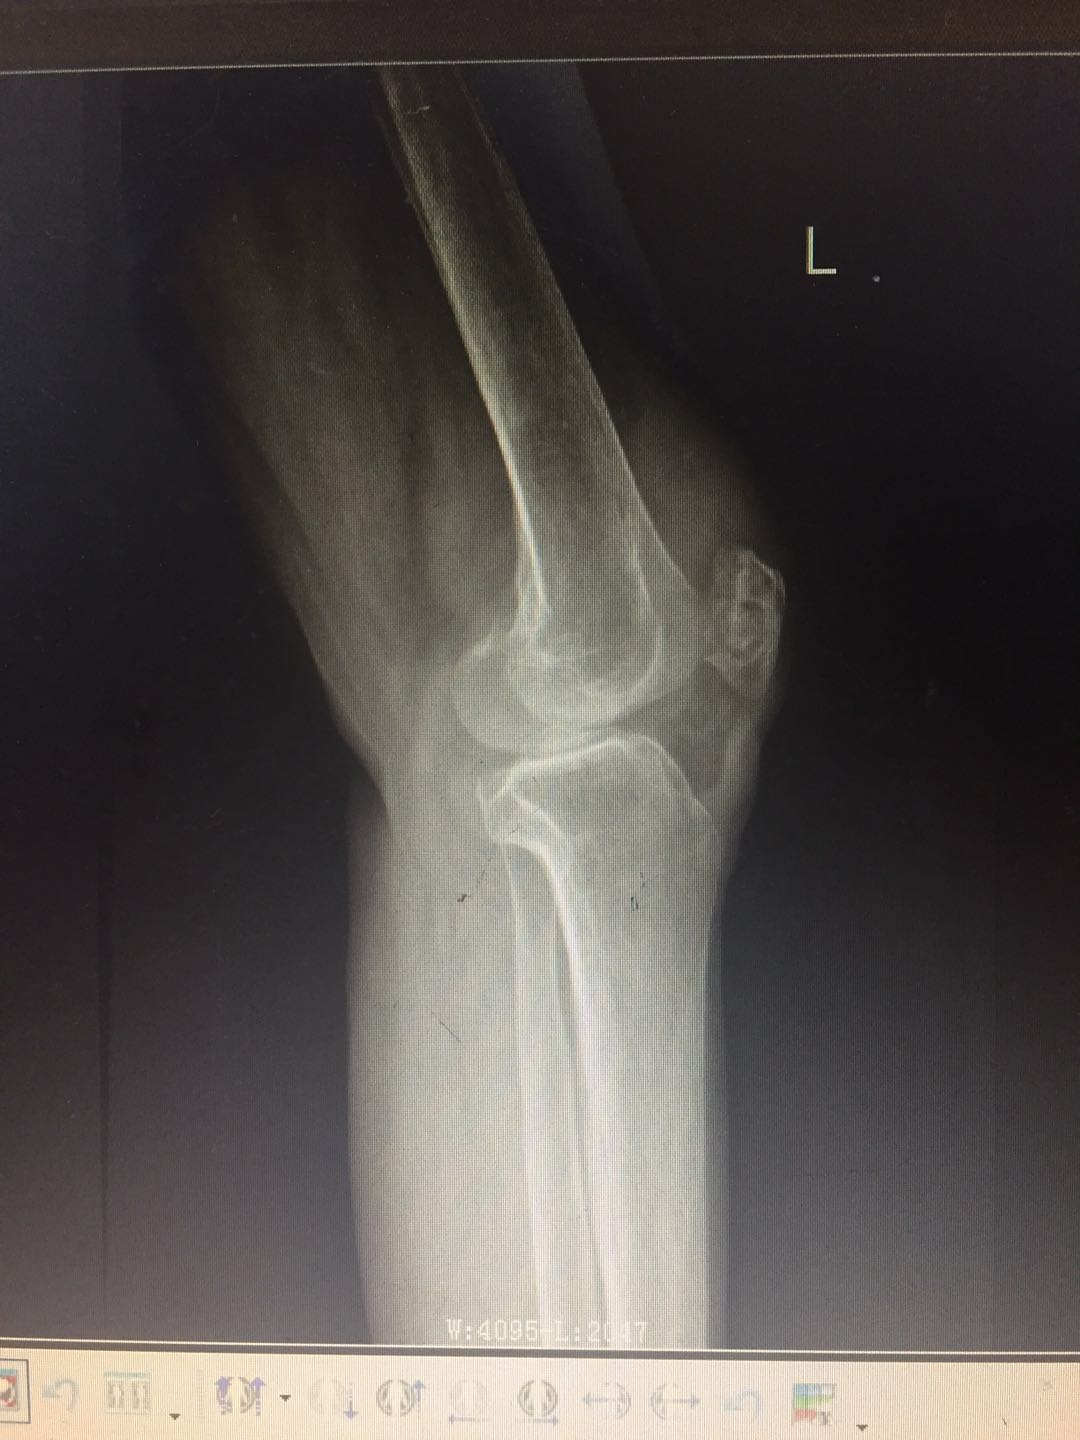

患 者:曾某某 ,女,69岁。

主 诉:左膝疼痛、肿胀、活动受限2年,加重3月,入院治疗。

专科检查:左膝部皮温稍增高,皮肤无发红,中度肿胀,呈屈曲位,内侧膝关节间隙处压痛明显,屈伸活动受限,被动活动时疼痛加重,左膝浮髌试验阳性,侧方挤压试验阳性,研磨试验阳性,抽屉试验阴性,肢端觉血运尚可,左下肢肌力感觉未见明显异常。

辅助检查:血沉:37mm/h,C反应蛋白:75.8ng/L,结核杆菌:阴性,降钙素原正常。余检查未见明显异常。

影像资料:

诊 断:

左膝骨性关节炎(K-L分级 4级);

左膝关节滑膜炎并关节积液。